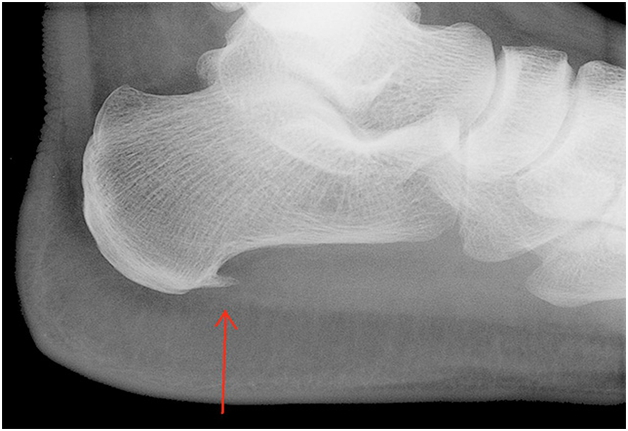

- рентгенография стоп;

Выявить шпору, образовавшуюся из-за отложения солей кальция, несколько сложнее. Рентгеновский снимок покажет ее как продолжение пяточной кости.